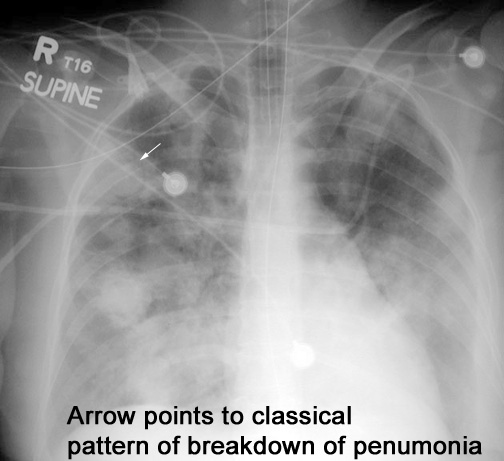

Case 20 Labeled Image List organisms causing necrotizing pneumonia leading to cavitation.